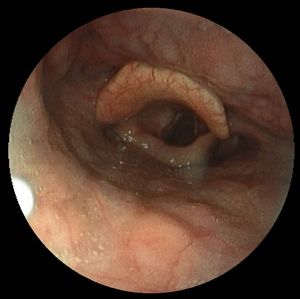

- 노인 후두는 나이가 들면서 후두 연조직이 위축되어 목소리가 약해지고 음성 범위와 지구력이 제한되는 질환이다. 후두경 검사에서 성대 앞부분에 활 모양 변형이 발견된다.